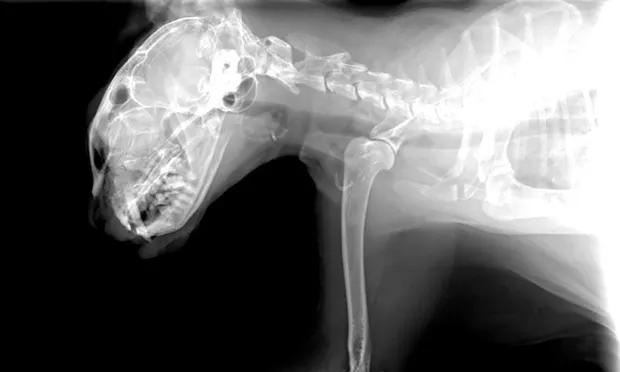

As in the majority of trauma cases, radiographs of the patient’s thorax and abdomen may be indicated. Skull radiographs provide little information regarding the severity of brain injury but may reveal structural damage such as fractures, especially if a physical defect in the skull is noted during physical examination. Testing such as computed tomography and magnetic resonance imaging may be required to further investigate the severity of brain injury.